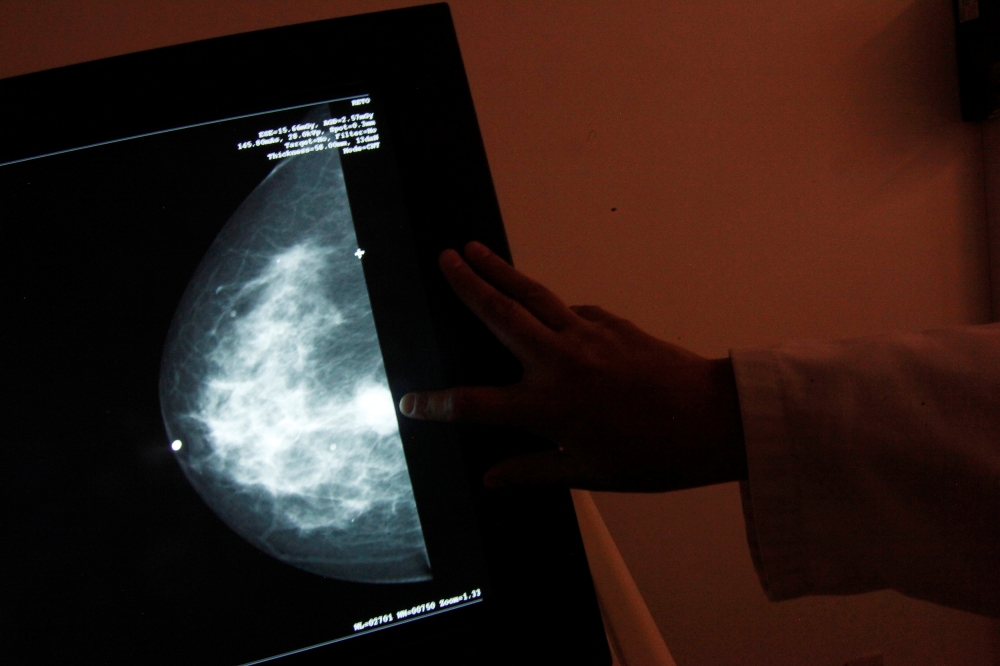

A monitor shows the image of a breast cancer at a centre run by the

A monitor shows the image of a breast cancer at a centre run by the "Reto" Group for Full Recovery of Breast Cancer in Mexico City October 18, 2012. Reuters/Edgard Garrido